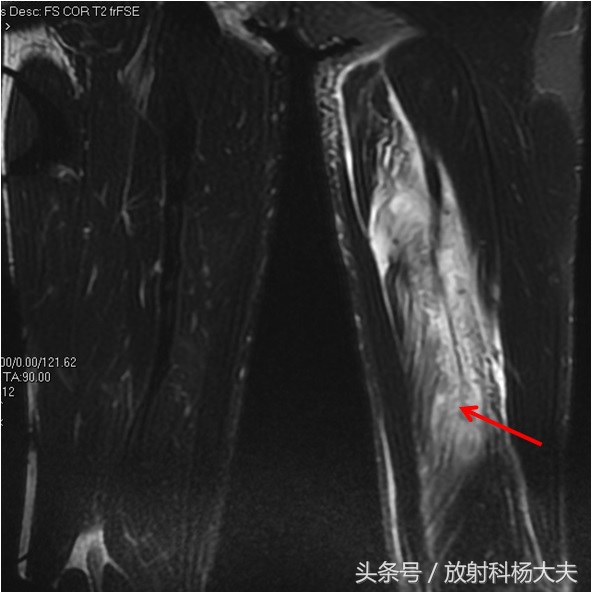

肌肉的损伤,轻度可表现为肌肉拉伤,在MRI上可仅仅有肌肉的水肿,水肿在MRI的T2WI图像上为高信号。严重者可以肌肉断裂,在MRI上也表现为连续性中断,多出现在肌肉和肌腱的连接处。也有的表现为肌肉或肌肉之间的血肿,当然,血肿也完全可以是迟发性的。当时没事,过两天出来了。

此图为一跳高运动员的大腿伤,红箭为半腱肌的拉伤,像羽毛状的高信号。